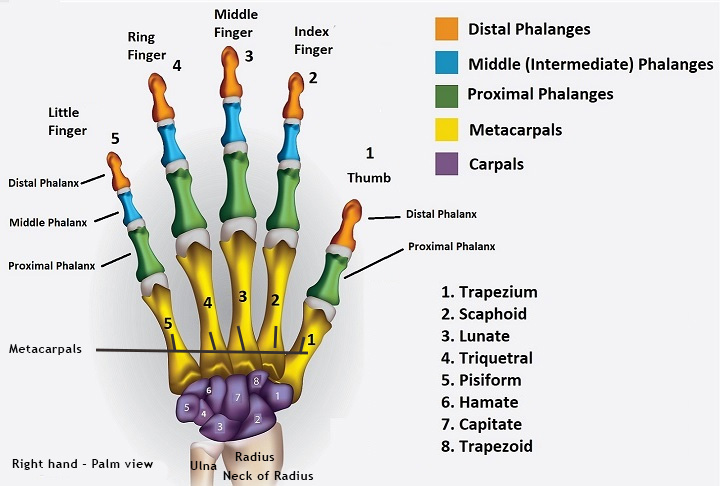

Problems involving the wrist and hand are increasingly common. They are often due to a fall or fracture and also due to repetitive strain syndromes. Sometimes they involve an arthritic pathology. Mostly they are amenable to mobilization of the joints and stretching of the tendons and muscles of the wrist and hand. I have special expertise in this area having treated many classical musicians for example.

Look at the incredible array of muscles in your forearm. I still marvel at the complexity which enables us to perform so many functions with our hands.

I had a case a month ago of a young guitarist who could no longer use his left little finger properly. I attended to the muscles and tendons which control that finger and improvement followed immediately. With computer workers I will examine their workstation set up and habits especially of mouse usage. This approach combined with my specialized techniques all to often bring about a rapid improvement.

We can all experience nerve related symptoms. Ranging from pins and needles, numbness and partial paralysis of muscles and limbs. Most of these common symptoms can be relieved by the correct diagnosis and treatment. The more serious central nervous system conditions are more problematic but can still be greatly helped especially with their secondary symptoms such as weakness, loss of co-ordination and worse. The most common nerve related symptom is pins and needles in the hand. This may be due to a number factors and is often mis-diagnosed as carpal tunnel syndrome.

Research on the beneficial effects of massage. Research collated from around the world.  Common wrist and finger joint problems Common wrist and finger joint problems The most vulnerable joint in the body.  Do you have Carpal Tunnel Syndrome? Do you have Carpal Tunnel Syndrome? A commonly mis-diagnosed problem.  Euronews: Generation Z+ Euronews: Generation Z+ How those of us in "Generation Z+" are facing the challenge of digital ageism.  Musicians Clinic